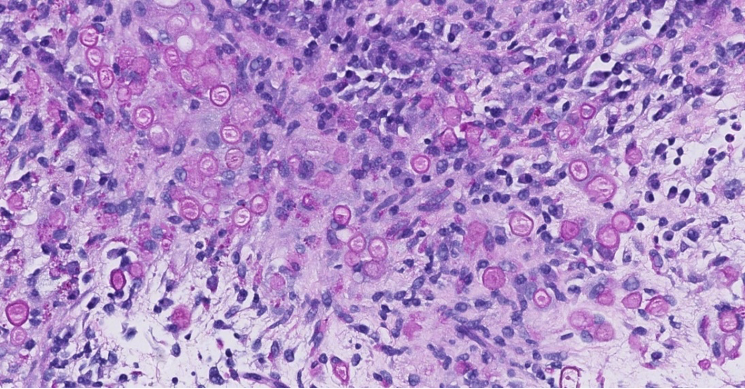

Figure 2. HE

Histologically, Liesegang rings appear as variably sized round structures with a laminated or ring-like configuration and may contain a central dense core. This pattern might result from alternating precipitation and diffusion of supersaturated solutions around a central amorphous nidus. They are typically PAS or DPAS positive and negative for calcium stains such as Von Kossa, helping to distinguish them from calcified structures.

In the present case, the radiologic finding of a PET-avid renal mass raised concern for metastatic disease or primary renal malignancy. However, histologic examination demonstrated a chronic lymphohistiocytic inflammatory process without evidence of malignancy. The presence of DPAS-positive concentric structures with negative Grocott and Von Kossa staining favored Liesegang rings rather than parasitic structures or malakoplakia.